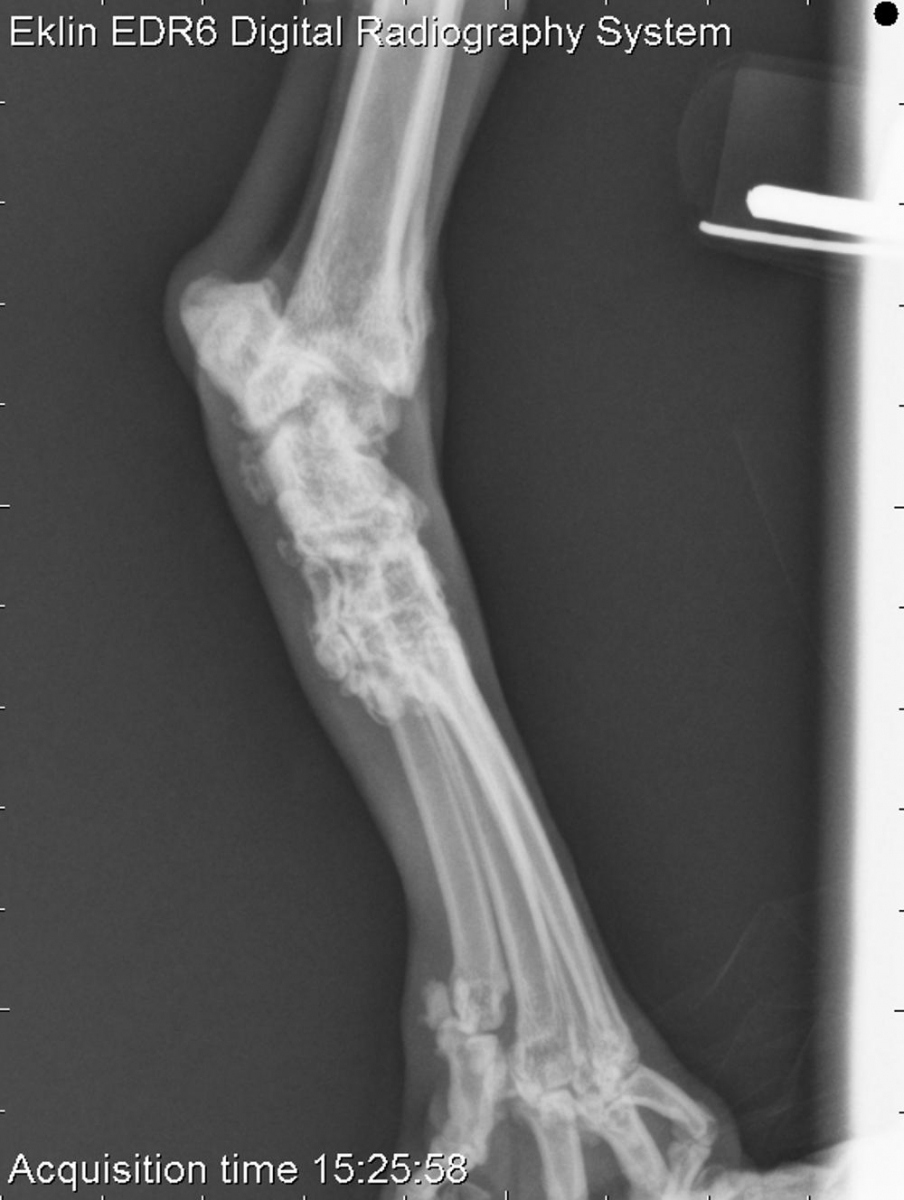

Today’s case is a 6 year old female neutered domestic medium hair cat with bilateral pelvic limb lameness. What are your findings and differential diagnoses?

There is bilateral tarsal effusion affecting all joints, particularly within the tibiotarsal joint. There is extensive periarticular osteophyte formation with relatively smooth margination. The tarsal bones appear heterogeneous.

• Polyarthritis, feline progressive polyarthritis.

Joint fluid analysis was declined by the owners, and no definitive diagnosis was obtained.